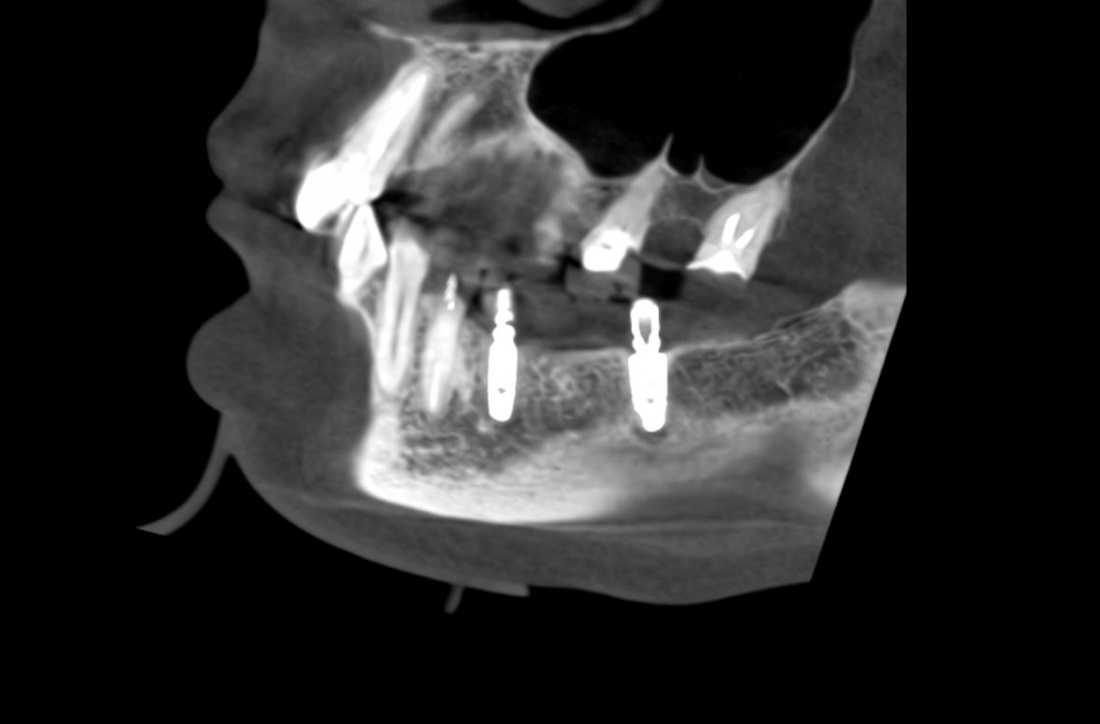

Простой. Надежный. Дешевый. Способ остеопластики.